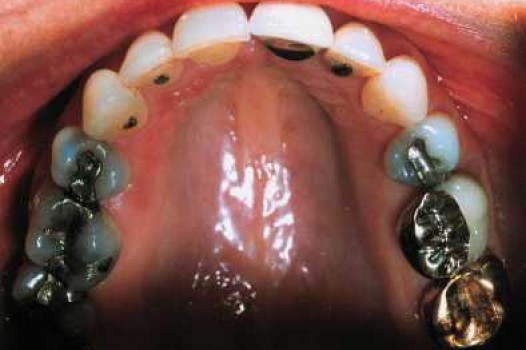

A Safer, Stronger Alternative to Mercury Fillings

Traditional amalgam (mercury) fillings have been used for over a century, but concerns about health risks, tooth fractures, and long-term decay have led many dentists to adopt modern alternatives. Today, metal-free restorations offer healthier, stronger, and more natural-looking results.

Using advanced resins, ceramics, and state-of-the-art bonding techniques, Dr. Klim can restore teeth with precision, preserving healthy tooth structure while preventing fractures, bacterial invasion, and future toothaches.